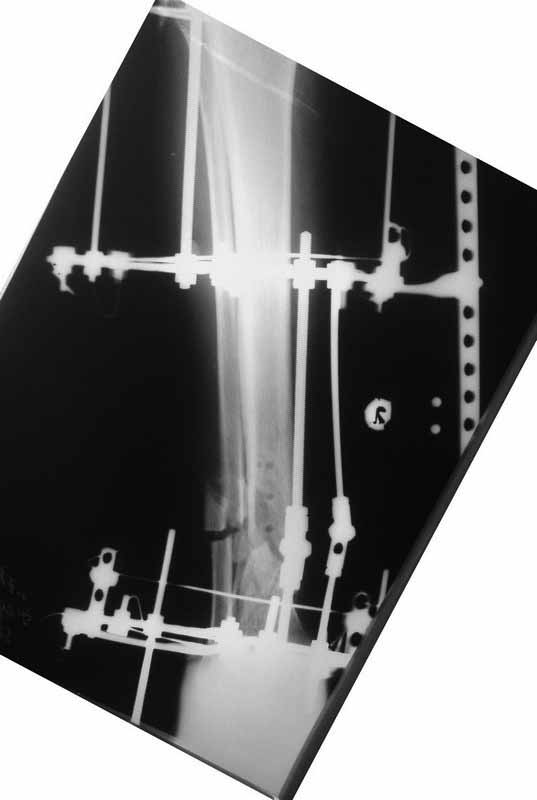

Да уж! Ни один из 3-х оперативных методов предшествующего лечения не был исполнен правильно. Везде был серьезный брак. Хотя любой из методов вполне мог бы и должен был бы привести к сращению,...если бы, да кабы.. В результате имеем то, что имеем. Что делать? Во-первых - подумать. Во-вторых - еще раз подумать. В третьих - еще больше подумать.

Иван, Вам видится зона перелома мертвой, а мне вовсе нет. Есть ли возможность сделать сцинтиграфию с технецием? Это может доказать нежизнеспособность или воспаление концов. Тогда есть резон для такой "крайней" меры как резекция. Есть ли клинические признаки инфекции в области первичной раны?, п\операционных рубцов?, в местах проведения спиц (нет ли спицевого остеомиелита)?.. В общем, вопросов может быть много.

Если нет данных за инфекцию в зоне перелома мы бы аппараптом дозированно устранили деформацию и, не удаляя дистальный фрагмент сломанного гвоздя, закрыто, после рассверливания заштифтовали бы достаточно толстым и надлежащей длины гвоздем.... Если есть спицевой остеомиелит, то также сначала аппарат, затем рассверливанме и цементный спейсор с а\б согласно посевам, через 2-3 недели удалить спейсор, повторно рассверлить и заштифтовать штифтом, возможно покрытым антибиотиком. А если Вы умело владеете техникой Илизарова, и больной согласен, можете оставить аппарат как окончательный метод фиксации....

В любом случае, если нет инфекции в зоне несращения и кость жизнеспособна, упаси Вас Бог что либо открывать и добавлять свободную костную пластику. Надо попытаться все сделать закрыто. Если откроете, то через пару месяцев, а может и раньше, все закончится резекцией и значительно большей чем 4 см...

Если там инфекция, что не исключено, судя по представленным данным, то вариантов нет - резекция в пределах здоровой кости.